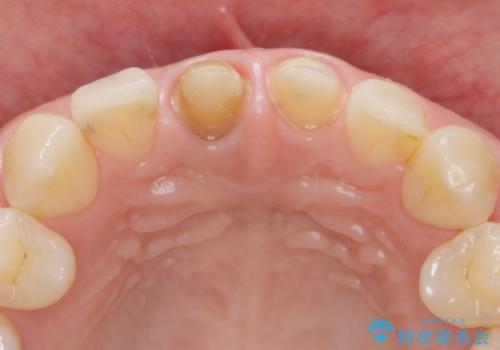

X線検査を行ったところ、共に深い虫歯が原因となり神経が死んでしまっている状態であることがわかり、根管治療を行ったのちセラミック補綴を行っていくこととなりました。

最終的なセラミッククラウンの精度・色調は非常に大事ですが、そこに至るまでの根管内環境の洗浄、ファイバーコアによる緊密な封鎖も長期的な予後に重要であると考えます。